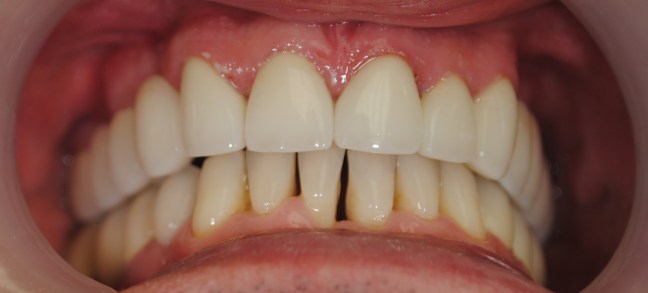

Kozmetikai kezelés: régi tömött, szuvasodott frontfogak szanálása, koronával történő leplezése, megsüllyedt harapás korrekciója.

A választott korona típusa: E-max préskerámia (fémmentes) és cirkon szóló koronák kombinációja.

A választott fogszín A1 .

A protetikai munka elkészülésének ideje: 5 munkanap.